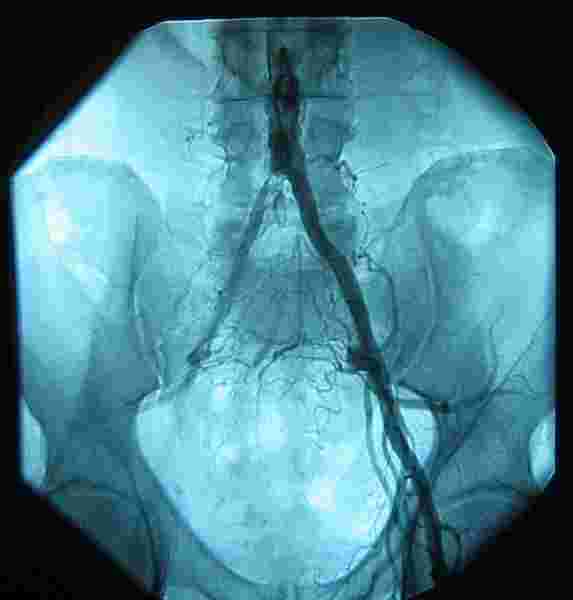

All living tissue requires oxygenated blood obviously. We are uncertain whether the death of this hip happened because of the slow loss of blood supply due to severe atherosclerotic furring of the aorta, caused by cigarette smoking, or from the operation to replace that part of the abdominal aorta that "dissected", at only 38 years of age. A transient loss of blood supply during the operation?

Either way, smoking is a deadly habit causing death and disability of millions.

Prior to the operation, she had no hip pain. Now, some thirty years later she is fairly disabled. Total hip replacement is on the cards, but she fears anaesthetic alzheimers. Meantime, hip exercises; she's coping and comes every six weeks for a chiropractic consultation.

A relatively uncommon but very painful condition called intermittent claudication is important to consider; it's a blocked artery in the groin; it happens in smokers usually with a poor diet.

I write about it simply because today I had a patient with groin pain whose leg pain symptoms are brought on with exercise, and immediately relieved by rest. Muscles in motion need more oxygen; at rest they don't complain.

He is forty seven years old and has been doing the medical rounds for six months, unable to sport and even walking more than a couple hundred metres.

The preliminary examination reveals all; no pulse in the ankle and foot; it took a chiropractor to think of the condition, and check the pulses.

Intermittent claudication doesn't need hip exercises and certainly doesn't need anyone messing around in the groin. If the clot breaks free, it goes straight to the lungs, heart or brain.